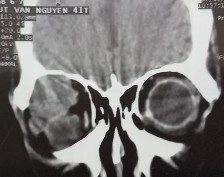

Bệnh nhân nam, 41 tuổi, MP: lồi mắt

Chẩn đoán MP: U hỗn hợp tuyến lệ lành tính

Bệnh nhân lồi mắt xuất hiện 3 năm, tăng nhanh trong vòng 1 năm trước vào viện, đẩy nhãn cầu xuống dưới (A). Hình ảnh cắt lớp vi tính có khối tăng ti trọng, bờ dày đều, kích thước 27 x 38 mm (C, D). Bệnh nhân được phẫu thuật cắt bỏ u cả khối gồm cả vỏ (E). Kết quả giải phẫu bệnh là hình ảnh biểu mô và trung mô của u hỗn hợp tuyến lệ lành tính (F: H&E x 100).